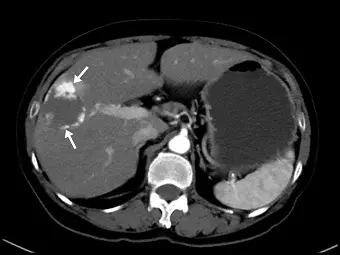

肝血管瘤( hepatic hemangioma )患者,接受三相( triple-phase )對比劑顯影的電腦斷層檢查,其病灶如下圖箭號所示,此圖最可能是什麼相的影像?

觀察題目提供的腹部軸切面(Axial)CT影像,可以發現以下幾個關鍵特徵:

- 降主動脈(Descending aorta):呈現極高的顯影密度(非常白),代表對比劑目前正大量集中於動脈系統中。

- 脾臟(Spleen):呈現斑駁、花斑狀或虎斑狀的顯影(Mottled / Tiger-stripe enhancement)。這是由於脾臟的紅髓與白髓血流灌注速度不同,在早期動脈相所呈現的典型特徵。

- 肝臟實質(Liver parenchyma):整體顯影程度仍偏低(暗),代表來自門靜脈的對比劑尚未大量進入肝臟微血管網。

- 病灶特徵(白色箭號處):肝臟右葉有一個低密度病灶,其邊緣出現不連續的結節狀強化(Peripheral discontinuous nodular enhancement)。此特徵其顯影密度與主動脈相近,為肝血管瘤在早期動脈相的經典表現。